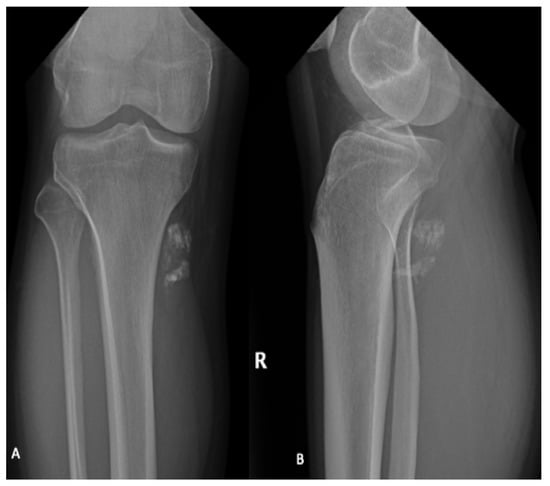

Plain radiographs are not required for diagnosis but are typically performed as part of the initial workup and can identify adjacent bony remodeling, bone invasion or calcification of the soft tissue mass (Figure 1) [,,]. Typically, synovial sarcoma presents as a well-defined or lobulated soft tissue mass on plain radiographs. Punctate calcifications, particularly around the periphery of the lesion, are visualized in one third of patients []. Occasionally, more extensive calcification can be visualized and can mimic bone forming tumors including osteosarcoma and myositis ossificans [].

Figure 1.

AP (A) and lateral (B) radiographs of the right (R) knee and lower leg in a 31-year-old male demonstrate coarse calcifications within the soft tissues adjacent to the posteromedial tibial plateau, corresponding to a biopsy proven synovial sarcoma. No significant articular abnormality. Adjacent bony structures appear unremarkable.